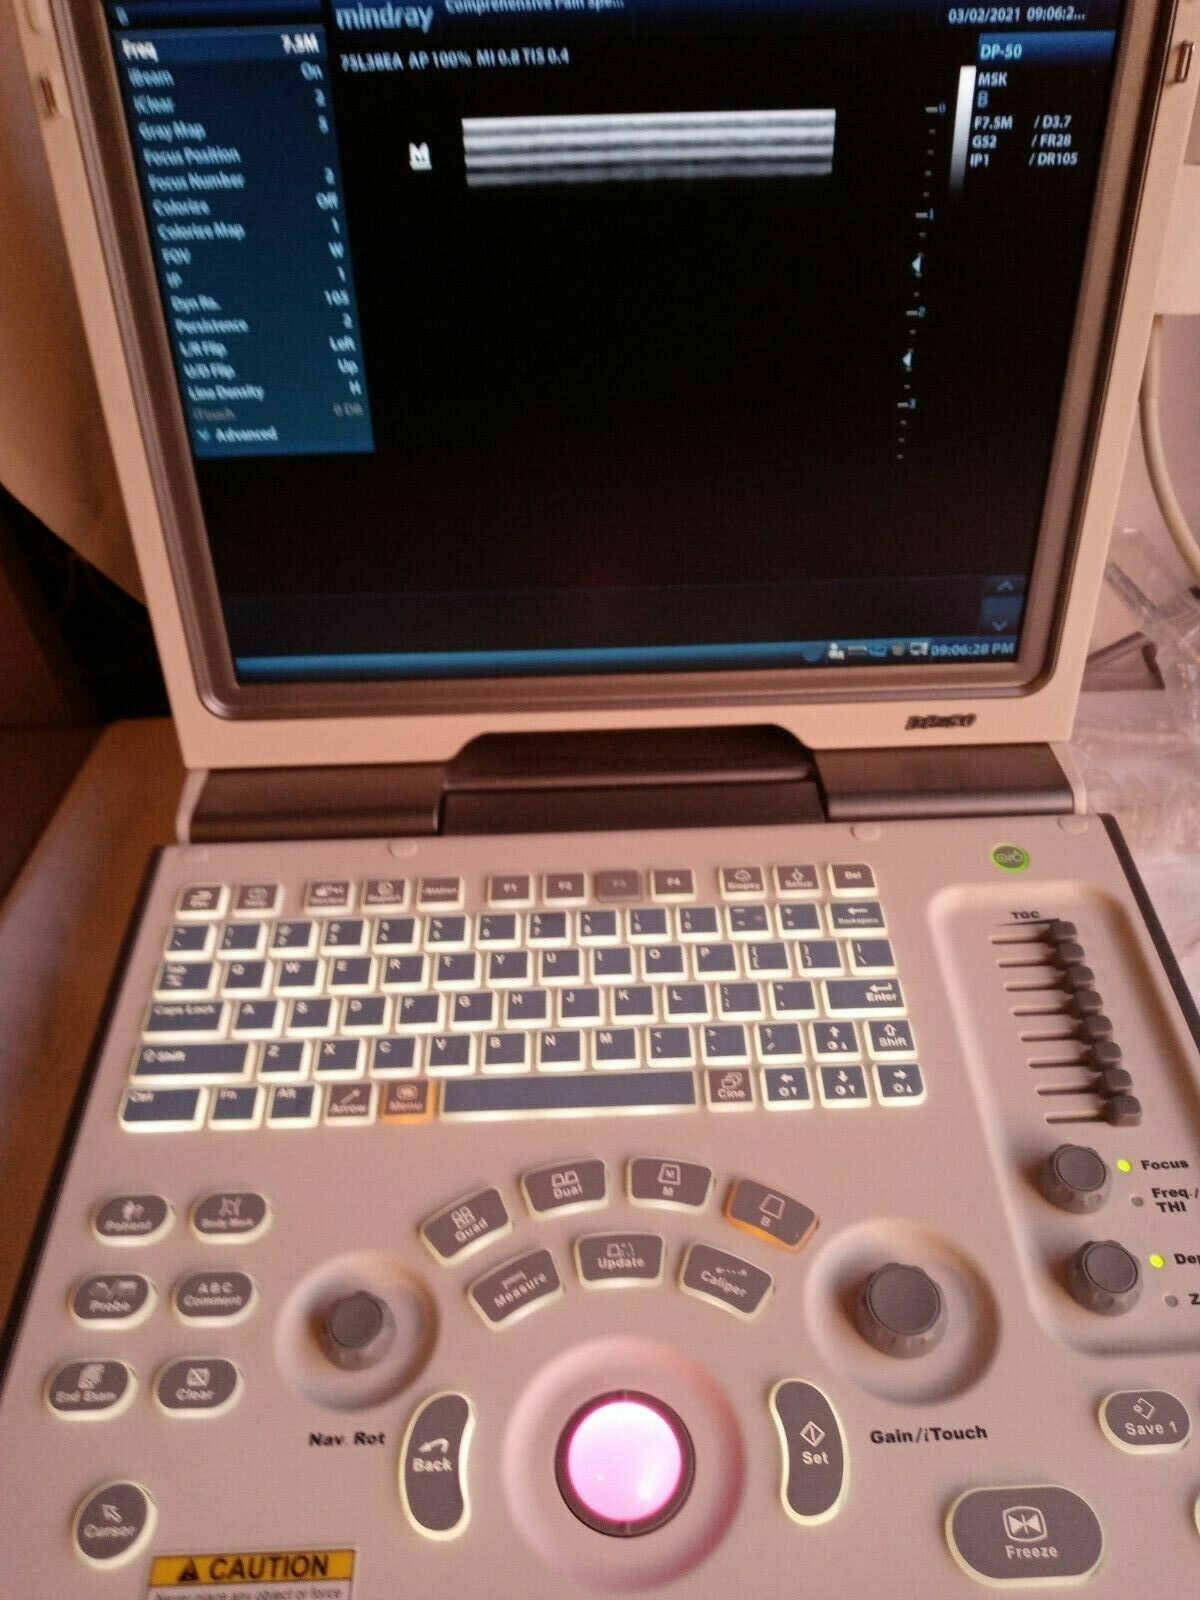

MINDRAY DIGITAL ULTRASOUND DIAGNOSTIC IMAGING SYSTEM,GREAT CONDITION(DP-50)

Sale price$ 5,250.00

Regular price$ 5,600.00

MINDRAY DP-50 PORTABLE ULTRASOUND WITH ONE CHOICE PROBE 1 YEAR WARRANTY

Sale price$ 5,998.00

Regular price$ 6,398.00

Save $ 676.00

MINDRAY DP-50 ULTRASOUND SYSTEM WITH ONE TRANSDUCER

Sale price$ 10,132.00

Regular price$ 10,808.00

Mindray DP-50 Ultrasound with Linear Transducer

Sale price$ 19,743.99

Save $ 170.00

Mindray DP50 Ultrasound with Convex Probe 35C50EA

Sale price$ 8,248.00

Regular price$ 8,798.00

Save $ 700.00

Mindray DP50 Ultrasound with Linear Array Probe 75L38EA

Sale price$ 10,498.00

Regular price$ 11,198.00